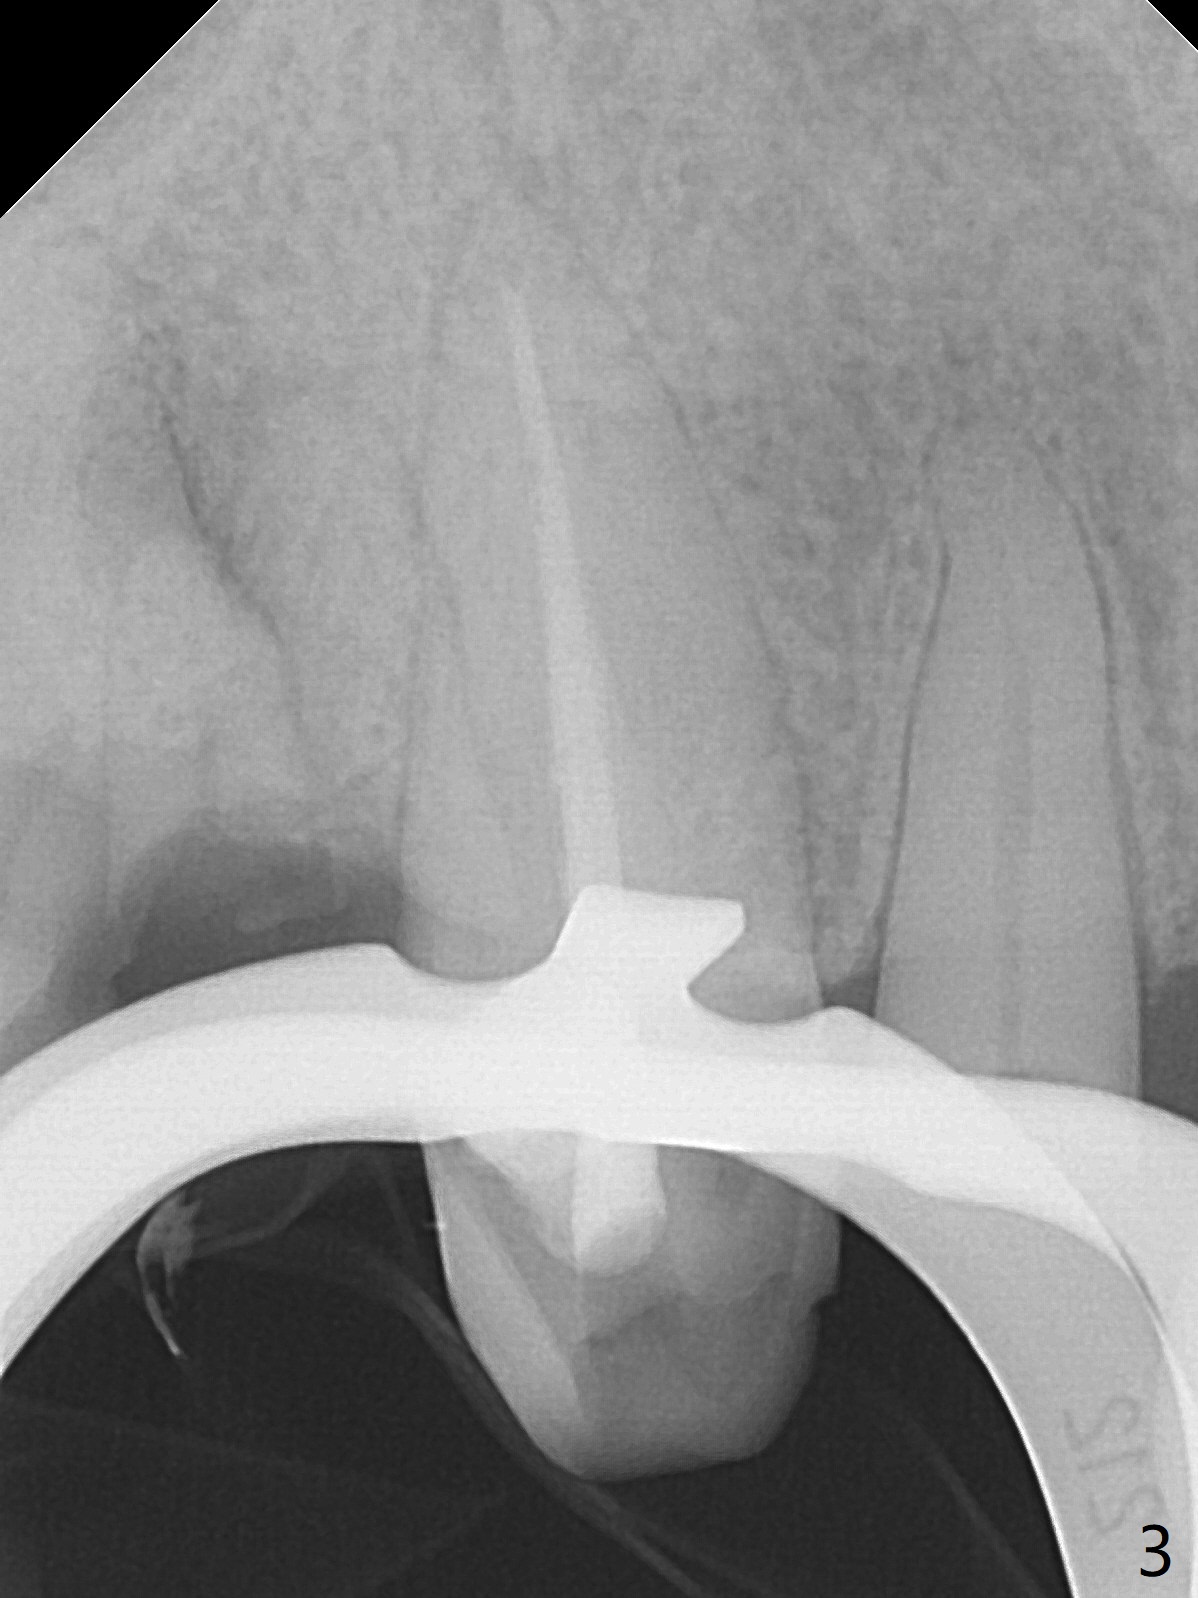

A 79-year-old man, who fractured the tooth #7, has several Class V defects (Fig.1). He seems to be a bruxer. Pay attention to occlusion and determine whether he has anterior deep bite. The neighboring tooth, #6, has apical lesion (Fig.2 <). Root canal therapy has been finished prior to implant placement (Fig.3). Prepare Tatum 1-piece implant in case the trajectory is off. If the crown height is more than 10 mm, prepare IS system. Otherwise use DIO one. If the root turns out to be difficult to extract, be ready for socket shield. Preop CT shows minimal apical perforation at #7 (Fig.4 (3-D image)). The buccal plate is thin (Fig.5 (coronal section) between arrowheads (acute infection may increase the perforation quickly)), while the crest is thick (*).